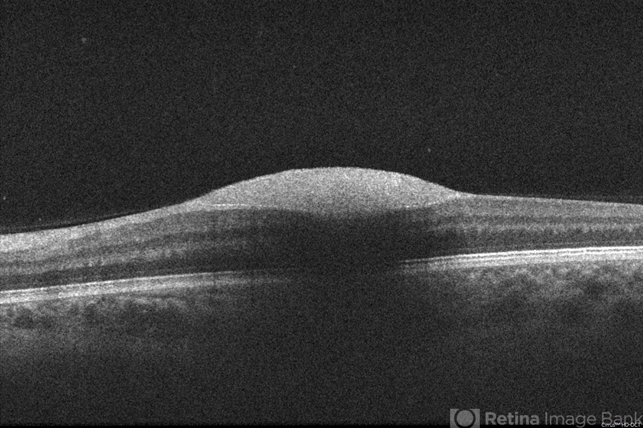

- 34-year old woman with preretinal hemorrhage in the macula, with dehemoglobinization occuring within the central portion of the hemorrhage while undergoing observation.